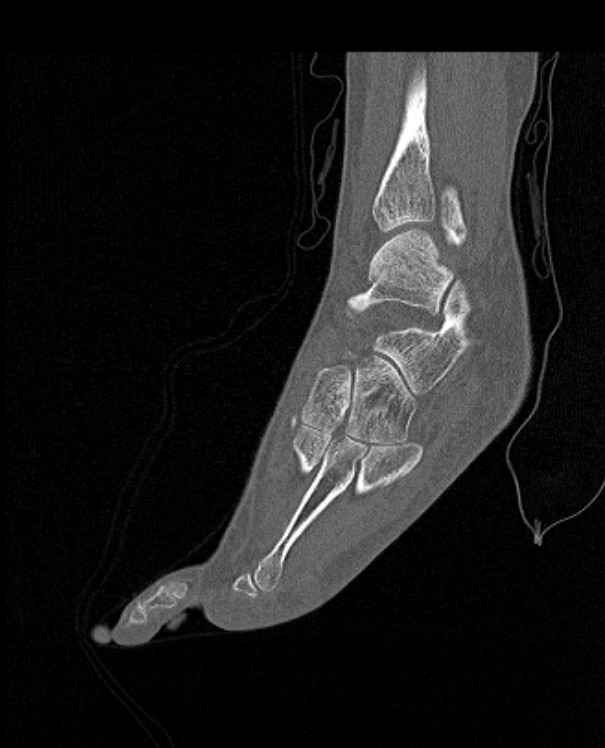

Стопа является самой удаленной частью нижней конечности и состоит из трех отделов: предплюсны, плюсны и собственно пальцев. Стопа представляет собой целый комплекс костей, соединенных между собой посредством тугих суставов.

Благодаря особенностям строения костей, а также наличию прочных связок, крепких мышц и сухожилий, стопа имеет сводчатую форму. Различают продольные своды и поперечный свод, которые обеспечивают эластичность стопы и ее амортизирующие свойства при ходьбе.

Наиболее точным и информативным методом обследования костных структур стопы является мультиспиральная компьютерная томография. КТ относится к лучевым методам исследования, то есть для визуализации внутренних органов применяется сканирование при помощи рентгеновского излучения, а затем полученные данные проходят цифровую обработку. В результате получается объемная реконструкция исследуемой области, которую можно увеличить, повернуть в разные стороны, оценить расположение анатомических структур и измененных участков в пространстве.

С помощью мультиспиральной КТ проводится точная диагностика травм стопы, позволяющая оценить расположение костных отломков. Метод КТ применяется для визуализации костей стопы при планировании хирургического вмешательства, затем в послеоперационном периоде для оценки правильности репозиции костных отломков и для контроля процессов регенерации кости.

Метод КТ наибольшую информацию дает о состоянии костных структур, так как кости в большей степени поглощают рентгеновские лучи и поэтому хорошо видны на снимках. Для повышения диагностических возможностей метода, в частности, для улучшения визуализации мягких тканей, мышц и связочного аппарата дополнительно используется контрастное усиление.

- переломы и трещины костей с нарушением структур, образованием костных отломков и их смещением;

- полные и неполные вывихи;

- смещения суставных поверхностей;

- деформирующий остеоартроз;